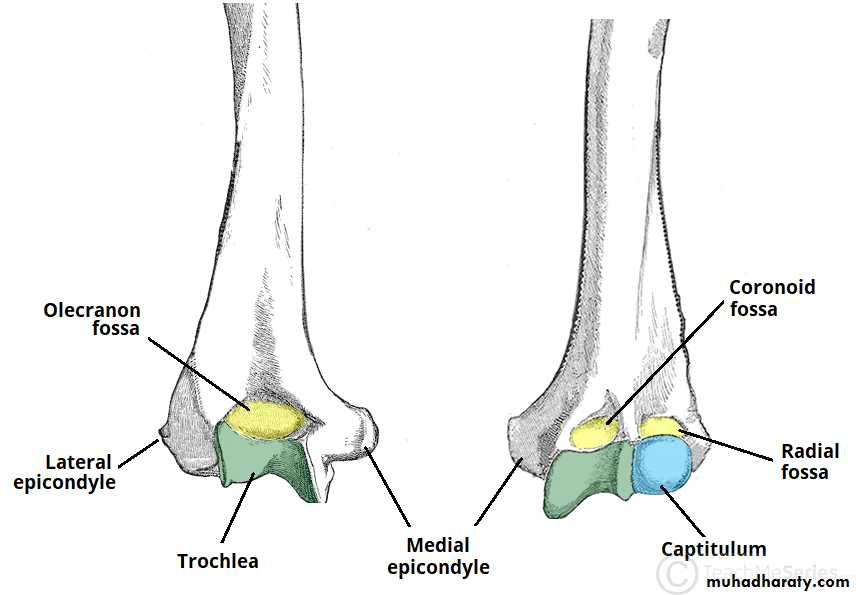

• عمليا يتم تصوير الرسغ والمرفق والكتف لمن يبدوا ظاهرا دون سن العشرين عاما من العمر. ويصور الحرقف لمن بدا في اواسط العقد الثالث من العمر او اقل, والنهاية الانسية للترقوة والتحام القص بالرهابة لمن تجاوز ذلك.

55• معدل ظهور والتحام المراكز التعظمية تبعا للعمر:

• 1) عند الولادة يظهر المركز التعظمي للنهاية السفلى للفخذ والمركز التعظمي لرأس عظم العضد.

• 2) في السنة الاولى( نهاية الشهر الثالث) يظهر (متع) للعظم الرؤيسي والشصي

• وفي الشهر السابع يظهر متع للنهاية السفلى للكعبرة, وفي الشهر العاشر يظهر

• متع للعظم المثلث من عظام الرسغ.

• 2) السنة الثانية يظهر المركز التعظمي للعظم الهلالي الرسغي.

• 3) في نهاية السنة الرابعة يظهر متع لرأس الكعبرة.

• 4) وفي بداية السنة الخامسة يظهر متع للعظم المربع المنحرف وفي نهاية السنة االخامسة يظهر المركز التعظمي لعظمي شبه المنحرف والزورقي الرسغيين.

• 5) في سن السادسة يظهر متع للقمة الانسية لعظم العضد والنهاية السفلية لعظم الزند.

6) في السنة الثامنة ونصف يظهر متع لبكرة العضد.

7) في نهاية السنة التاسعة يظهر متع للنتوء المرفقي لعظم الزند والعظم الحمصي.

8) في نهاية السنة العاشرة يظهر متع اللقمة الوحشية للعضد.

معدل التحام مراكز التعظم:

1) في سن 13-14 سنة تلتحم البكرة بعمد العضد.

2) في سن 14-15 يلتحم راس الكعبرة بالعمد والنتوء المرفقي بالزند.

3) في سن 16-17 سنة تلتحم اللقمة الانسية بعمد العضد.

574) في سن 17-18 تلتحم النهايتان السفليتان للكعبر والزند كل مع عمده.

5) في سن 18-19 يلتحم راس العضد بعمده.

6) وفي سن 25 سنة يلتحم عرف الحرقف بالحرقف والنهاية الانسية للترقوة بالترقوة.